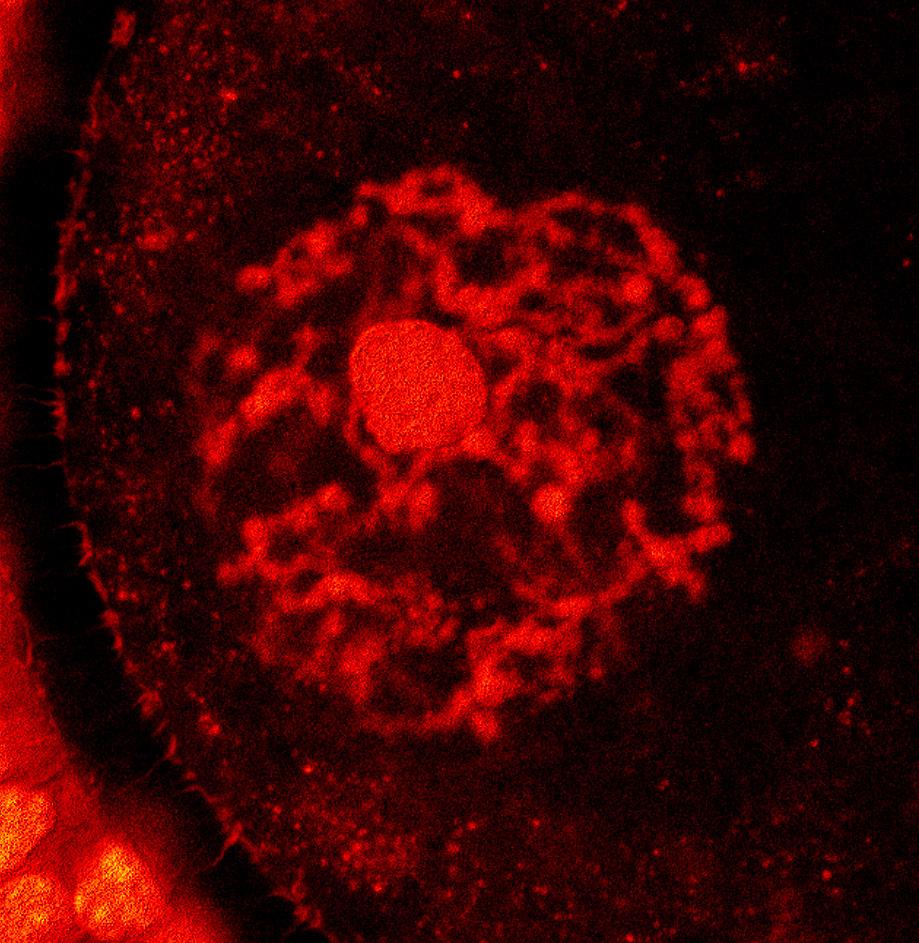

BRIEFING: It is now exactly 20 years since my colleague David Barad, MD, MS, and I published our first paper reporting on the potential fertility benefits of supplementing selected patients with DHEA (dehydroepiandrosterone). This and several quickly following papers on the same subject ended up changing infertility practice in many – maybe most – fertility clinics in the world (Reference 1). It was a paper reporting on a CHR patient in her early 40s who, completely unknown to us at the CHR, had started self-supplementing with DHEA because a first IVF cycle had yielded only one egg and one embryo. She had been advised that, assuming a similar second cycle, further repeat IVF cycles with the use of her own eggs would not make much sense anymore. She then, however, made us scratch our heads, - wondering what was going on - in subsequent back-to-back cycles, as the patient from cycle to cycle produced more and more oocytes and embryos. Only after her 6th consecutive cycle, did she finally clarify what was going on, when disclosing that she - completely on her own – had started supplementing with DHEA. It was this disclosure that then initiated years of DHEA-related research at the CHR, resulting in a large number of published studies in several leading peer-reviewed medical journals and – to this day – the only U.S. patents approved for claims of treatment benefits for androgens (including DHEA) supplementation in selected infertile women. On the occasion of this 20th anniversary, this article presents an update on the subject of androgen supplementation in selected infertile women, with special emphasis on DHEA supplementation.

the real study of androgens in female infertility only started in ca, 2004 at the CHR in NYC with because of a single patient who wanted to cryopreserve her eggs: This then 42-year old female patient with extremely low functional ovarian reserve (LFOR) – unknown to the center’s physicians – initiated self-supplementation with DHEA. She decided on supplementing with this hormone after researching the literature for compounds that might improve the dismal one oocyte yield she had produced in her first IVF cycle at the CHR.

Though in initial studies, we very quickly confirmed the beneficial effects of DHEA supplementation on several outcome parameters in infertile women with low androgen levels, we made only slow progress in our understanding of how these outcome improvements came about. But that changed very quickly when Aritro Sen, PhD, and Stephen R. Hammes, MD in 2010 reported a mouse study in which they had knocked out androgen receptors on granulosa cells and oocytes and noticed that the knockouts on granulosa cells severely interrupted follicle maturation, while receptor knock out on oocytes showed hardly any effects.2

fully corresponded with the clinical data the CHR’s investigators had reported. And these animal data were not only restricted to mouse models but also included larger animal models, including sheep and monkey models. All uniformly confirmed that good/normal testosterone levels were essential during small follicle-growing stages (i.e., between secondary and small antral follicles) in synergistically with FSH, supporting follicle growth and maturation. Too low androgens reduced egg numbers as well as egg quality. Proper supplementation of abnormally low androgens leads to normal testosterone levels, then, however, reconstitutes more and betterquality oocyte yields, leading to more pregnancies and fewer miscarriages.